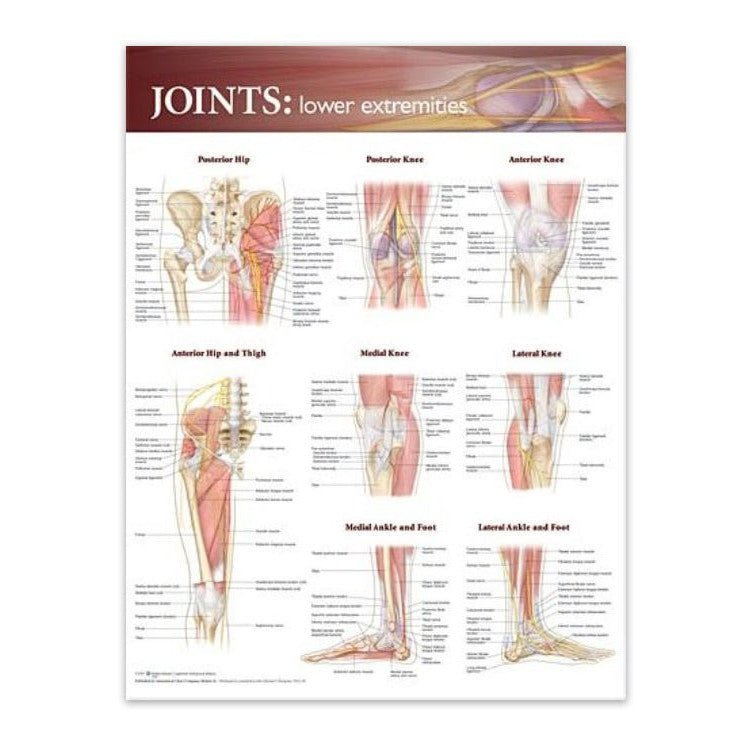

Muscle posters

Muscles provide movement to the musculoskeletal system, and their origins, insertions and lodges are clinically important for every healthcare professional. That is why we at eAnatomi have both developed and designed our own anatomy posters, which provide the ultimate overview of all the muscles of the body. On this page you can find both our own posters and posters from other manufacturers. We offer posters in several different languages such as pure Latin, Danish, English and Swedish, etc.